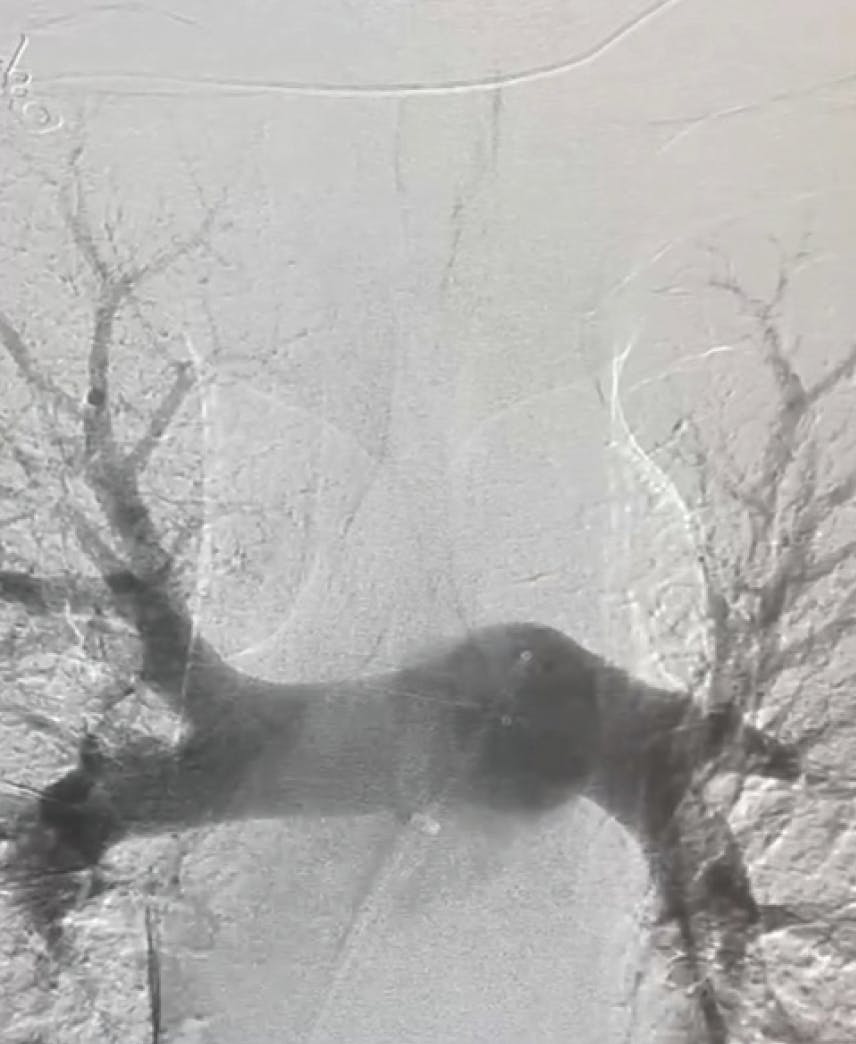

Figure 2. Left lobe initial angiogram.

Figure 2. Left initial angiogram.

Figure 1. Right and left initial angiograms.